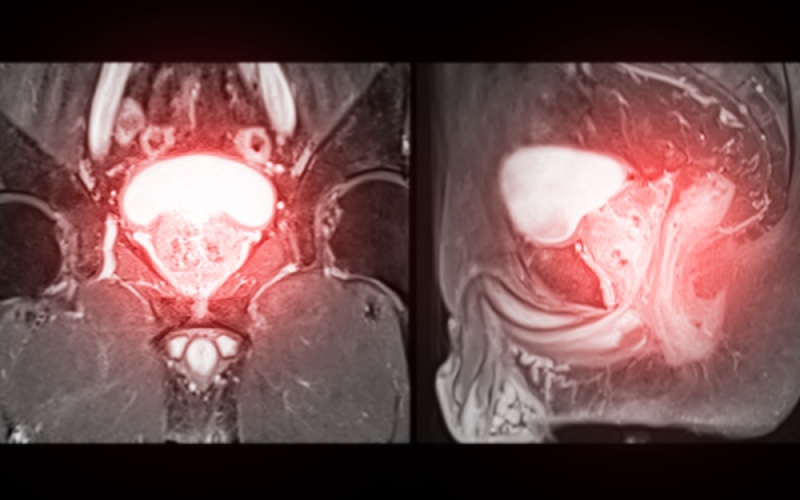

Tuyến tiền liệt là một tuyến đặc trưng chỉ có ở hệ sinh dục nam, có cấu tạo gồm mô cơ và mô tuyến. Vị trí của tuyến tiền liệt nằm ngay trước trực tràng – đoạn cuối của ruột già, bao quanh cổ bàng quang và đoạn đầu của niệu đạo. Tuyến có hình dạng giống hạt dẻ, bề mặt trơn láng, có rãnh giữa chia thành hai thùy gần như đối xứng, và có độ đàn hồi nhất định. (1)

Kích thước tuyến tiền liệt bao nhiêu là bình thường? Mức độ phì đại tuyến tiền liệt được coi là bình thường khi sự gia tăng kích thước diễn ra theo tiến trình lão hóa tự nhiên. Các nghiên cứu cho thấy tuyến tiền liệt thường có kích thước khoảng 25 – 30g ở nam giới ở độ tuổi 40. Khi bước sang độ tuổi 50, kích thước này có thể tăng lên 30 – 40g và tiếp tục đạt khoảng 35 – 45g ở độ tuổi 60.

Đặc biệt, vùng chuyển tiếp của tuyến – khu vực xung quanh niệu đạo và thường là nơi bắt đầu của phì đại có thể tăng từ khoảng 15g ở tuổi 40 lên đến 25g ở tuổi 60 – 70. Đây là quá trình phì đại lành tính theo tuổi, không phải lúc nào cũng gây triệu chứng lâm sàng.

Phì đại tuyến tiền liệt có thể được phân loại theo thể tích tuyến dựa trên kết quả siêu âm. Ở mức nhẹ, tuyến tiền liệt có thể tích dưới 30ml, thường chưa gây ra triệu chứng lâm sàng rõ rệt. Trong khi đó, thể vừa được xác định khi tuyến có thể tích từ 30ml đến 80ml, có thể gây ra các rối loạn tiểu tiện mức độ trung bình và thường đáp ứng tốt với điều trị nội khoa. Trường hợp nặng, thể tích trên 80ml, nguy cơ tắc nghẽn đường tiểu tăng cao, điều trị nội khoa không mang lại hiệu quả, thường phải can thiệp ngoại khoa.